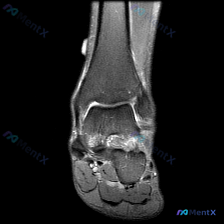

这是一张脚踝MRI冠状位T2序列影像,可见的解剖结构包括胫骨远端、腓骨远端、距骨及部分跟骨。

- 骨骼: 距骨上方穹窿区域可见大范围不均匀高信号,边缘欠清晰,提示软骨下骨骨髓水肿或炎性改变;胫骨、腓骨远端骨髓信号无明显异常

- 关节: 胫距关节腔内可见异常高信号液体充盈,提示中等量以上关节积液

- 软组织: 踝关节内侧三角韧带区域、外侧腓骨下方都可见软组织肿胀伴高信号,弥漫性水肿,内外侧均受累